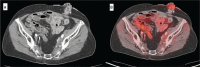

Results: Of the 160 IgG4-RD patients in this cohort, 36 (22.5%) had large-vessel involvement. The mean age at disease onset of the patients with large-vessel IgG4-RD was 54.6 years. Twenty-eight patients (78%) were male and 8 (22%) were female. Thirteen patients (36%) had primary IgG4-related vasculitis and aortitis with aneurysm formation comprised the most common manifestation. This affected 5.6% of the entire IgG4-RD cohort and was observed in the thoracic aorta in 8 patients, the abdominal aorta in 4, and both the thoracic and abdominal aorta in 3. Three of these aneurysms were complicated by aortic dissection or contained perforation. Periaortitis secondary to RPF accounted for 27 of 29 patients (93%) of secondary vascular involvement by IgG4-RD. Only 5 patients demonstrated evidence of both primary and secondary blood vessel involvement. Of those treated with rituximab, a majority responded positively.

Conclusions: IgG4-RD is a distinctive, unique, and treatable cause of large-vessel vasculitis. It can also involve blood vessels secondary to perivascular tumefactive lesions. The most common manifestation of IgG4-related vasculitis is aortitis with aneurysm formation. The most common secondary vascular manifestation is periaortitis with relative sparing of the aortic wall. Both primary vasculitis and secondary vascular involvement respond well to B cell depletion therapy.